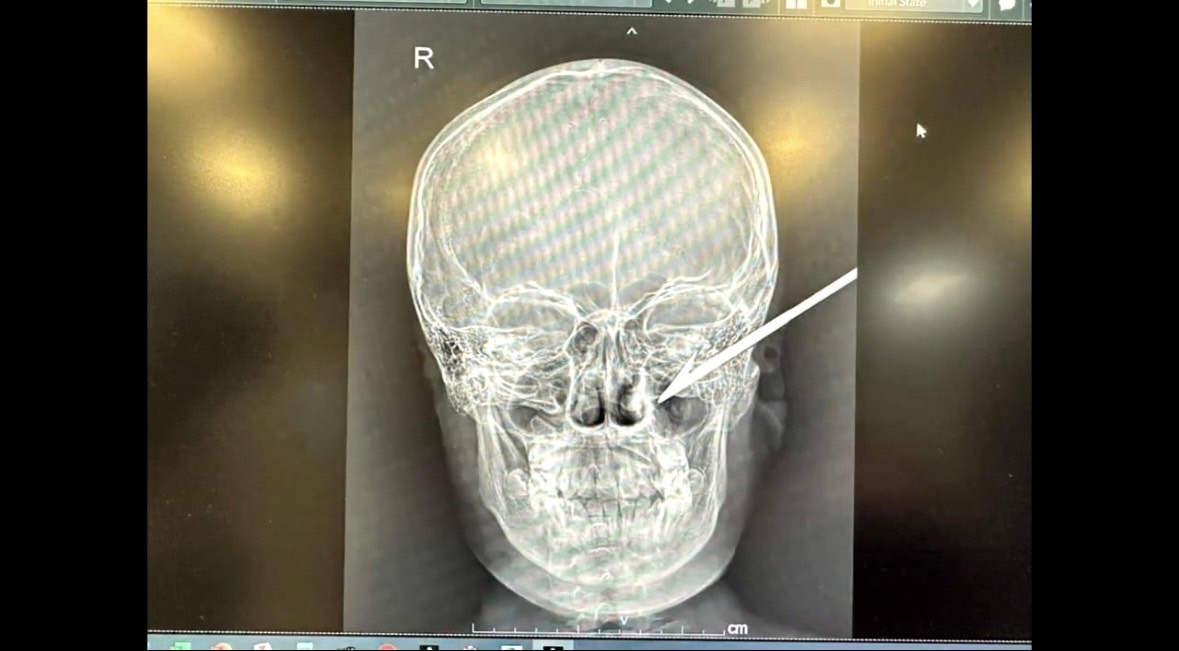

ทางมูลนิธิจึงนำอุปกรณ์เครื่องเครื่องตัดพลาสม่า พร้อมทีมกู้ชีพกู้ภัย ฮุก 31 เข้าสนับสนุน ซึ่งเมื่อไปถึง รพ.มหาราชฯ พบเด็กชายที่ได้รับบาดเจ็บ ชื่อ เด็กชายวันวรุณ คำมิทัน ชาว อ.ห้วยแถลง จ.นครราชสีมา นอนอยู่บนเตียงรถเข็นผู้ป่วย เมื่อตรวจสอบที่บริเวณใบหน้าและดูฟิล์มเอ็กซเรย์ พบว่า ส่วนหัวของลูกดอกยิงหนู เจาะทะลุที่ขมับด้านซ้าย ปักทแยงเยื้องไปทางโหนกแก้ม หวิดโดนลูกตาและสมอง โดยลูกดอกยังปักคาอยู่ โผล่ให้เห็นเฉพาะส่วนก้านและหางลูกดอกเท่านั้น

ซึ่งลูกดอกยิงหนูทำจากเหล็กเส้น มีความยาวประมาณ 2 ฟุต จึงวางแผนกับทีมเพื่อตัดปลายลูกดอกออกให้ปลอดภัยที่สุด เพื่อไม่ให้หัวศรของดูกดอกที่ยังปักคาอยู่ภายในกระทบอวัยวะที่สำคัญไปมากกว่านี้

เมื่อวางแผนเรียบร้อย จึงนำผ้ามาคลุมปิดบริเวณใบหน้าป้องกันไม่ให้สะเก็ดไฟ ที่เกิดจากการตัดเหล็กกระเด็นถูกใบหน้าจนเป็นบาดแผล เหลือเฉพาะบริเวณที่มีปลายลูกดอกโผล่ออกมาเท่านั้น จากนั้นนำอุปกรณ์เครื่องตัดพลาสมา มาตัดส่วนก้านและปลายลูกดอกออก ก่อนส่งต่อให้คณะแพทย์นำผู้ได้รับบาดเจ็บเข้าเครื่องซีทีสแกนอีกครั้งเพื่อดูบาดแผล และทำการผ่าตัดเอาส่วนที่เหลือออก